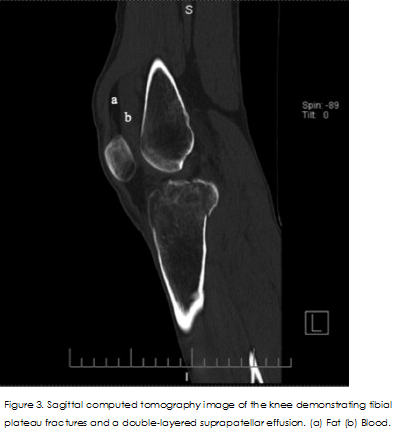

Cause Report